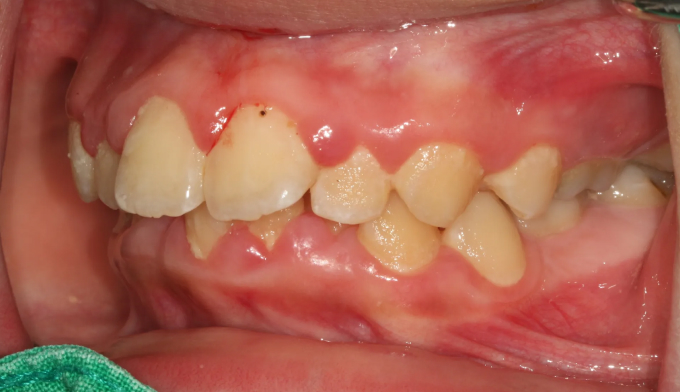

돌출입, 구강위생불량

Before

앞니가 돌출되어있고, 특히 전반적으로 양치질이 부족하여 잇몸이 모두 부어있는 상태입니다.

치아들의 배열이 고르지 못한 상태에서는 양치질이 더욱 어려워지므로 구강위생상태에 더 신경을 써야 합니다.